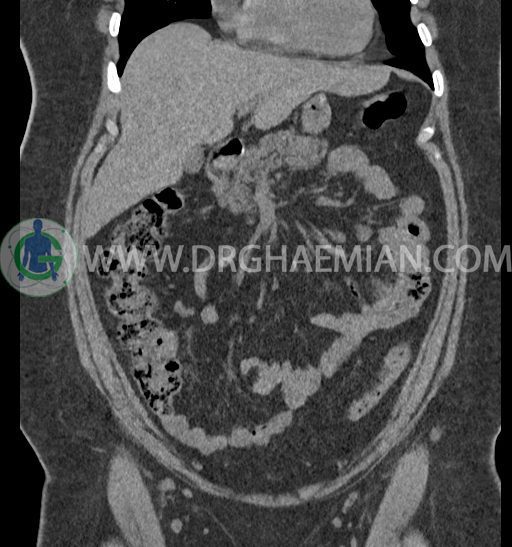

سی تی اسکن شکم و لگن با استفاده از اشعات ایکس تصاویر عرضی از ناحیه شکم و لگن ایجاد میکند. در این کیس کلیه نعل اسبی و سنگ کلیه مشاهده می شود.

در سی تی اسکن اسپیرال شکم و لگن بدون کنتراست (مولتی دیدکتور 16 با مقاطع ظریف و بازسازی های ساژیتال و کرونال) :

-horseshoe kidney

-حداقل سه سنگ 5mm در کلیه راست و یک سنگ 3mm در کلیه چپ بدون شواهدی از هیدرونفروز

-شواهد جراحی اسلیو قبلی در Body و فوندوس معده